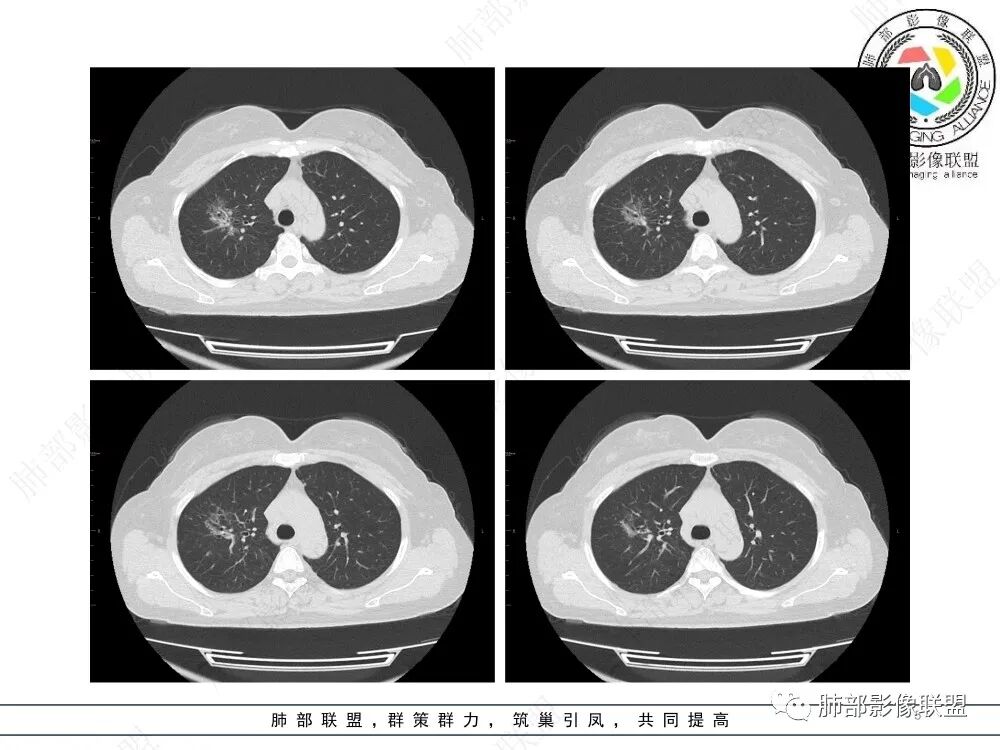

病例特点:52岁女性,体检患者。

影像特点:右肺上叶混合磨玻璃影,边界清晰,结构松散,内有多结节堆积及支气管扩张影,可见小叶间隔增厚,并局部增厚的小叶间隔上亦存在微结节,胸膜侧可见纤细索条,病灶周围可见多发微结节影。

总体分析:从病灶分布来看符合结核的好发位置,影像表现也符合结核的多态性,且出现卫星灶。由于有边界清晰的GGO,需要鉴别腺癌,虽然此病例有边界清晰的GGO,但是它的GGO的边缘有结节感,呈多结节堆积,而腺癌的GGO缺乏这种“多结节堆积感”,另外,此病例也没有发现腺癌的胸膜凹陷征、毛刺征及月牙铲等。